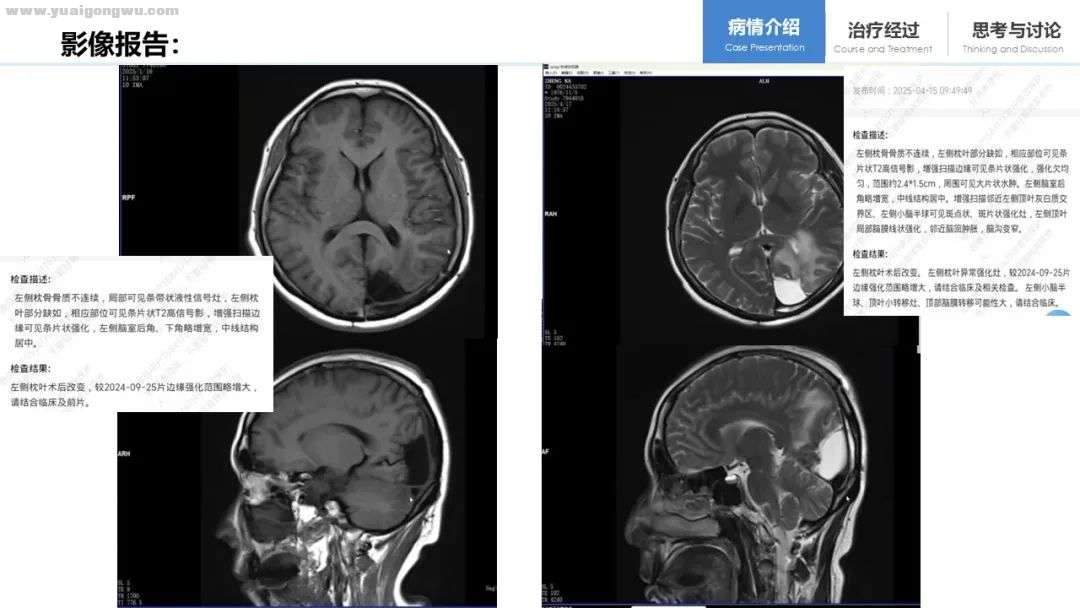

再看患者脑部核磁情况:2024年4月发现脑部单发转移灶并进行手术切除;2025年1月的核磁增强图像显示,手术切缘存在轻微强化,目前尚不能确定是否为手术遗留所致;2025年4月的核磁报告提示,该强化结节进一步增大;2025年5月的核磁报告显示,结节强化范围持续扩大,且出现小脑半球、顶叶及脑膜转移。综合这一系列脑部核磁检查结果可知,患者的脑部病变处于持续进展状态。

林根教授 从患者的影像学表现来看,临床诊断脑膜转移基本可确立,磁共振增强扫描显示多处脑膜存在强化。尽管患者已进行两次腰穿未发现癌细胞,但建议其前往更高一级医院,尤其是在脑膜转移诊疗方面经验丰富的机构重新进行腰穿检查。